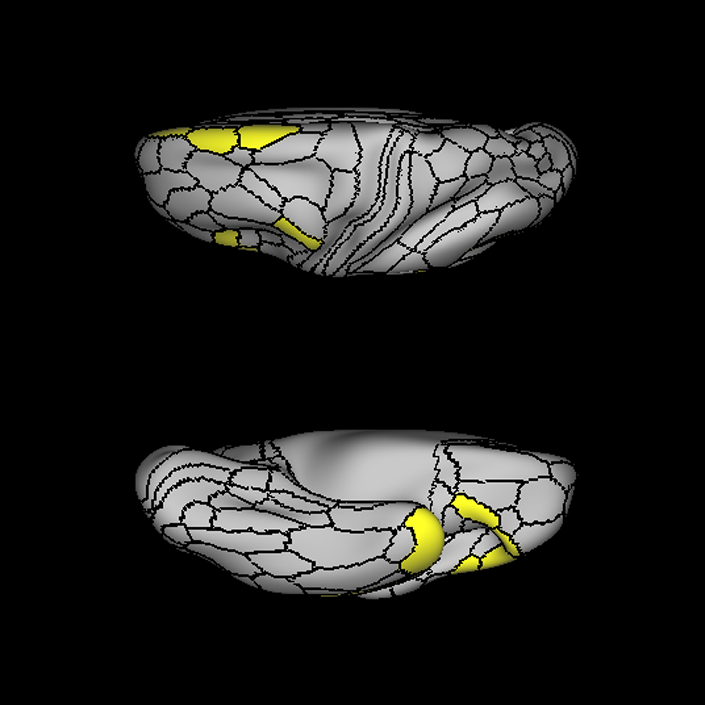

ᐅ SummaryArea 45: part of the inferior frontal gyrus of the lateral frontal lobe. In addition to its known association with Broca's area, is sometimes represented as part of Broca's complex ᐅ Where is it?Area 45 is the lateral surface of pars triangularis of the IFG. ᐅ What are its borders?Area 45 borders area 47L anteriorly and area 44 posteriorly. Its superior edge borders area p47r, IFSa, and IFSp. Its opercular surface is conveniently named FOP5 ᐅ What are its functional connections?Area 45 demonstrates functional connectivity to areas SFL, IFSp, 44, a47r, 47s, 47L, 9a, 9p, 9m, 8AV, and 8BL in the dorsolateral frontal lobe, area 8BM in the medial frontal lobe, area 55b in the premotor areas, areas FOP5, and PSL in the insula-opercular region, areas TGd, TGv, TE1a, STSva, STSdp and STSvp in the temporal lobe, area PGi in the inferior parietal lobe, and area 31pd in the medial parietal lobe. ᐅ What are its white matter connections?Area 45 is structurally connected to the arcuate/SLF and IFOF. However, arcuate/SLF connections are not consistent across individuals. Connections with the arcuate/SLF project posteriorly and wrap around the Sylvian fissure to the middle temporal gyrus to end at TE1p. There are also projections from the arcuate/SLF before it terminates to parcellations A4 and PBelt. IFOF connections travel from 45 through the extreme/external capsule and continue posteriorly through the temporal lobe to end at occipital lobe parcellations V1, V2, V3 and V4. Local short association bundles connect with 44 and FOP4. ᐅ What is known about its function?Area 45, in addition to its known association with Broca's area, is sometimes represented as part of "Broca's complex", including Brodmann Areas 45, 46, 47 and the mesial supplementary motor area of 6, which contribute to a frontal-subcortical circuit. |

A: lateral-medial

B: anterior-posterior

C: superior-inferior

DTI image |